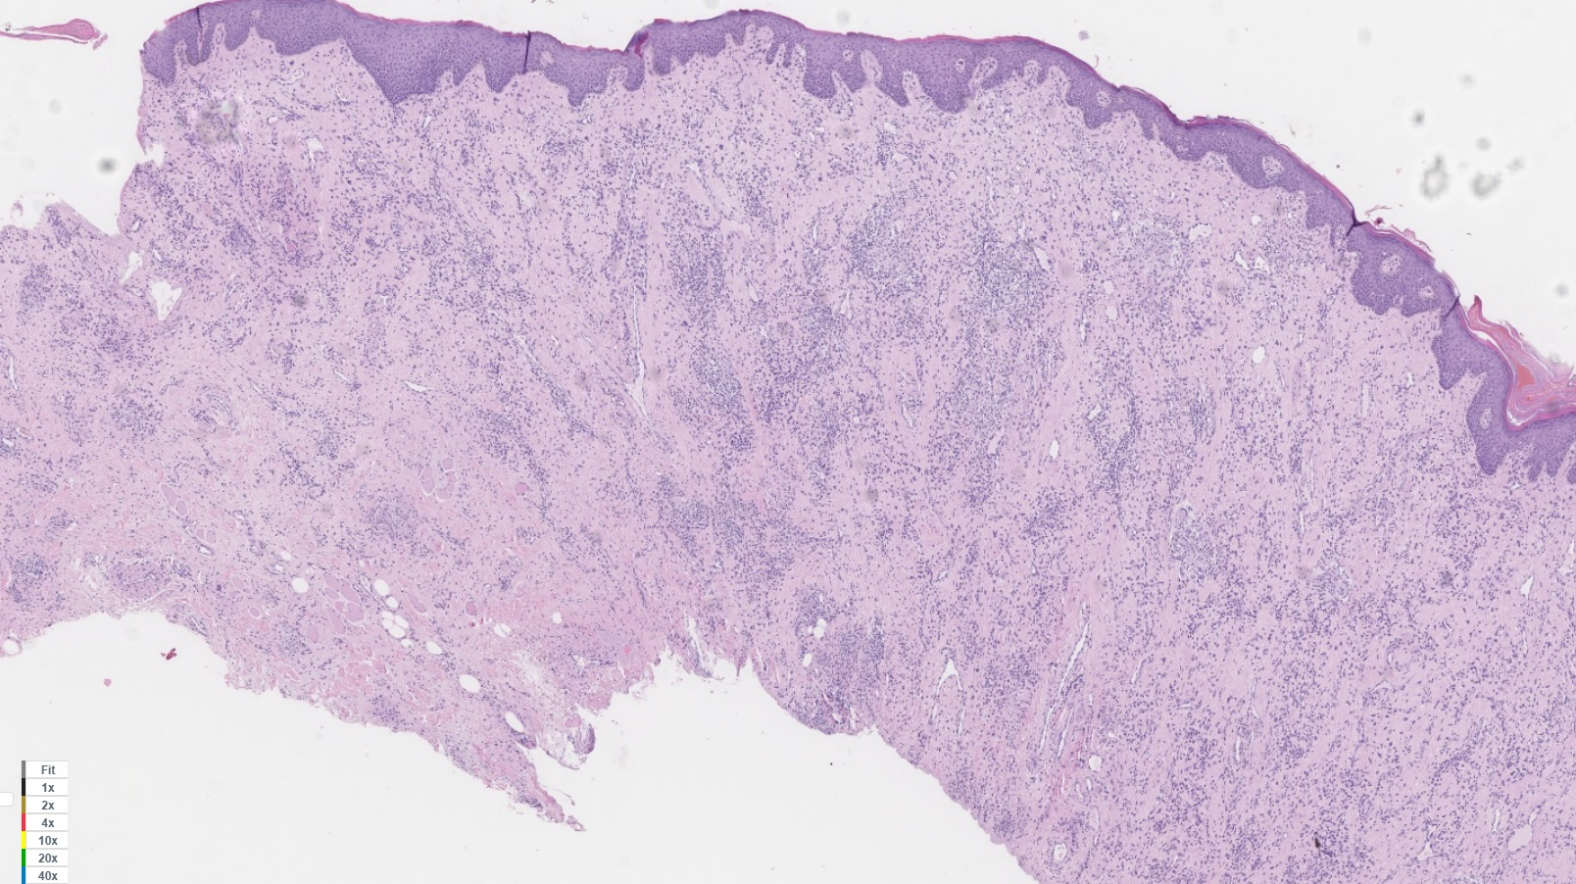

A histopathological study of the surgical specimens was undertaken, showing superficial and deep chronic perivascular inflammation associated to granulomas, consistent with orofacial granulomatosis (cheilitis granulomatosa) (Figure 4 [Fig. 4], Figure 5 [Fig. 5]).

Figure 4: In this histological image, a mucous layer with chronic lymphoplasmacitic infiltrate can be seen, with presence of noncaseating granulomas. Hematoxylin and eosin (H&E). 2x.

Figure 5: In this histological image, a mucous layer with chronic lymphoplasmacitic infiltrate can be seen, with presence of noncaseating granulomas. Hematoxylin and eosin (H&E). 20x.

The pathological study plays an important role in the diagnosis of the disease, showing presence of lymphedema and noncaseating granulomas in the lamina propria with chronic inflammatory response [2].